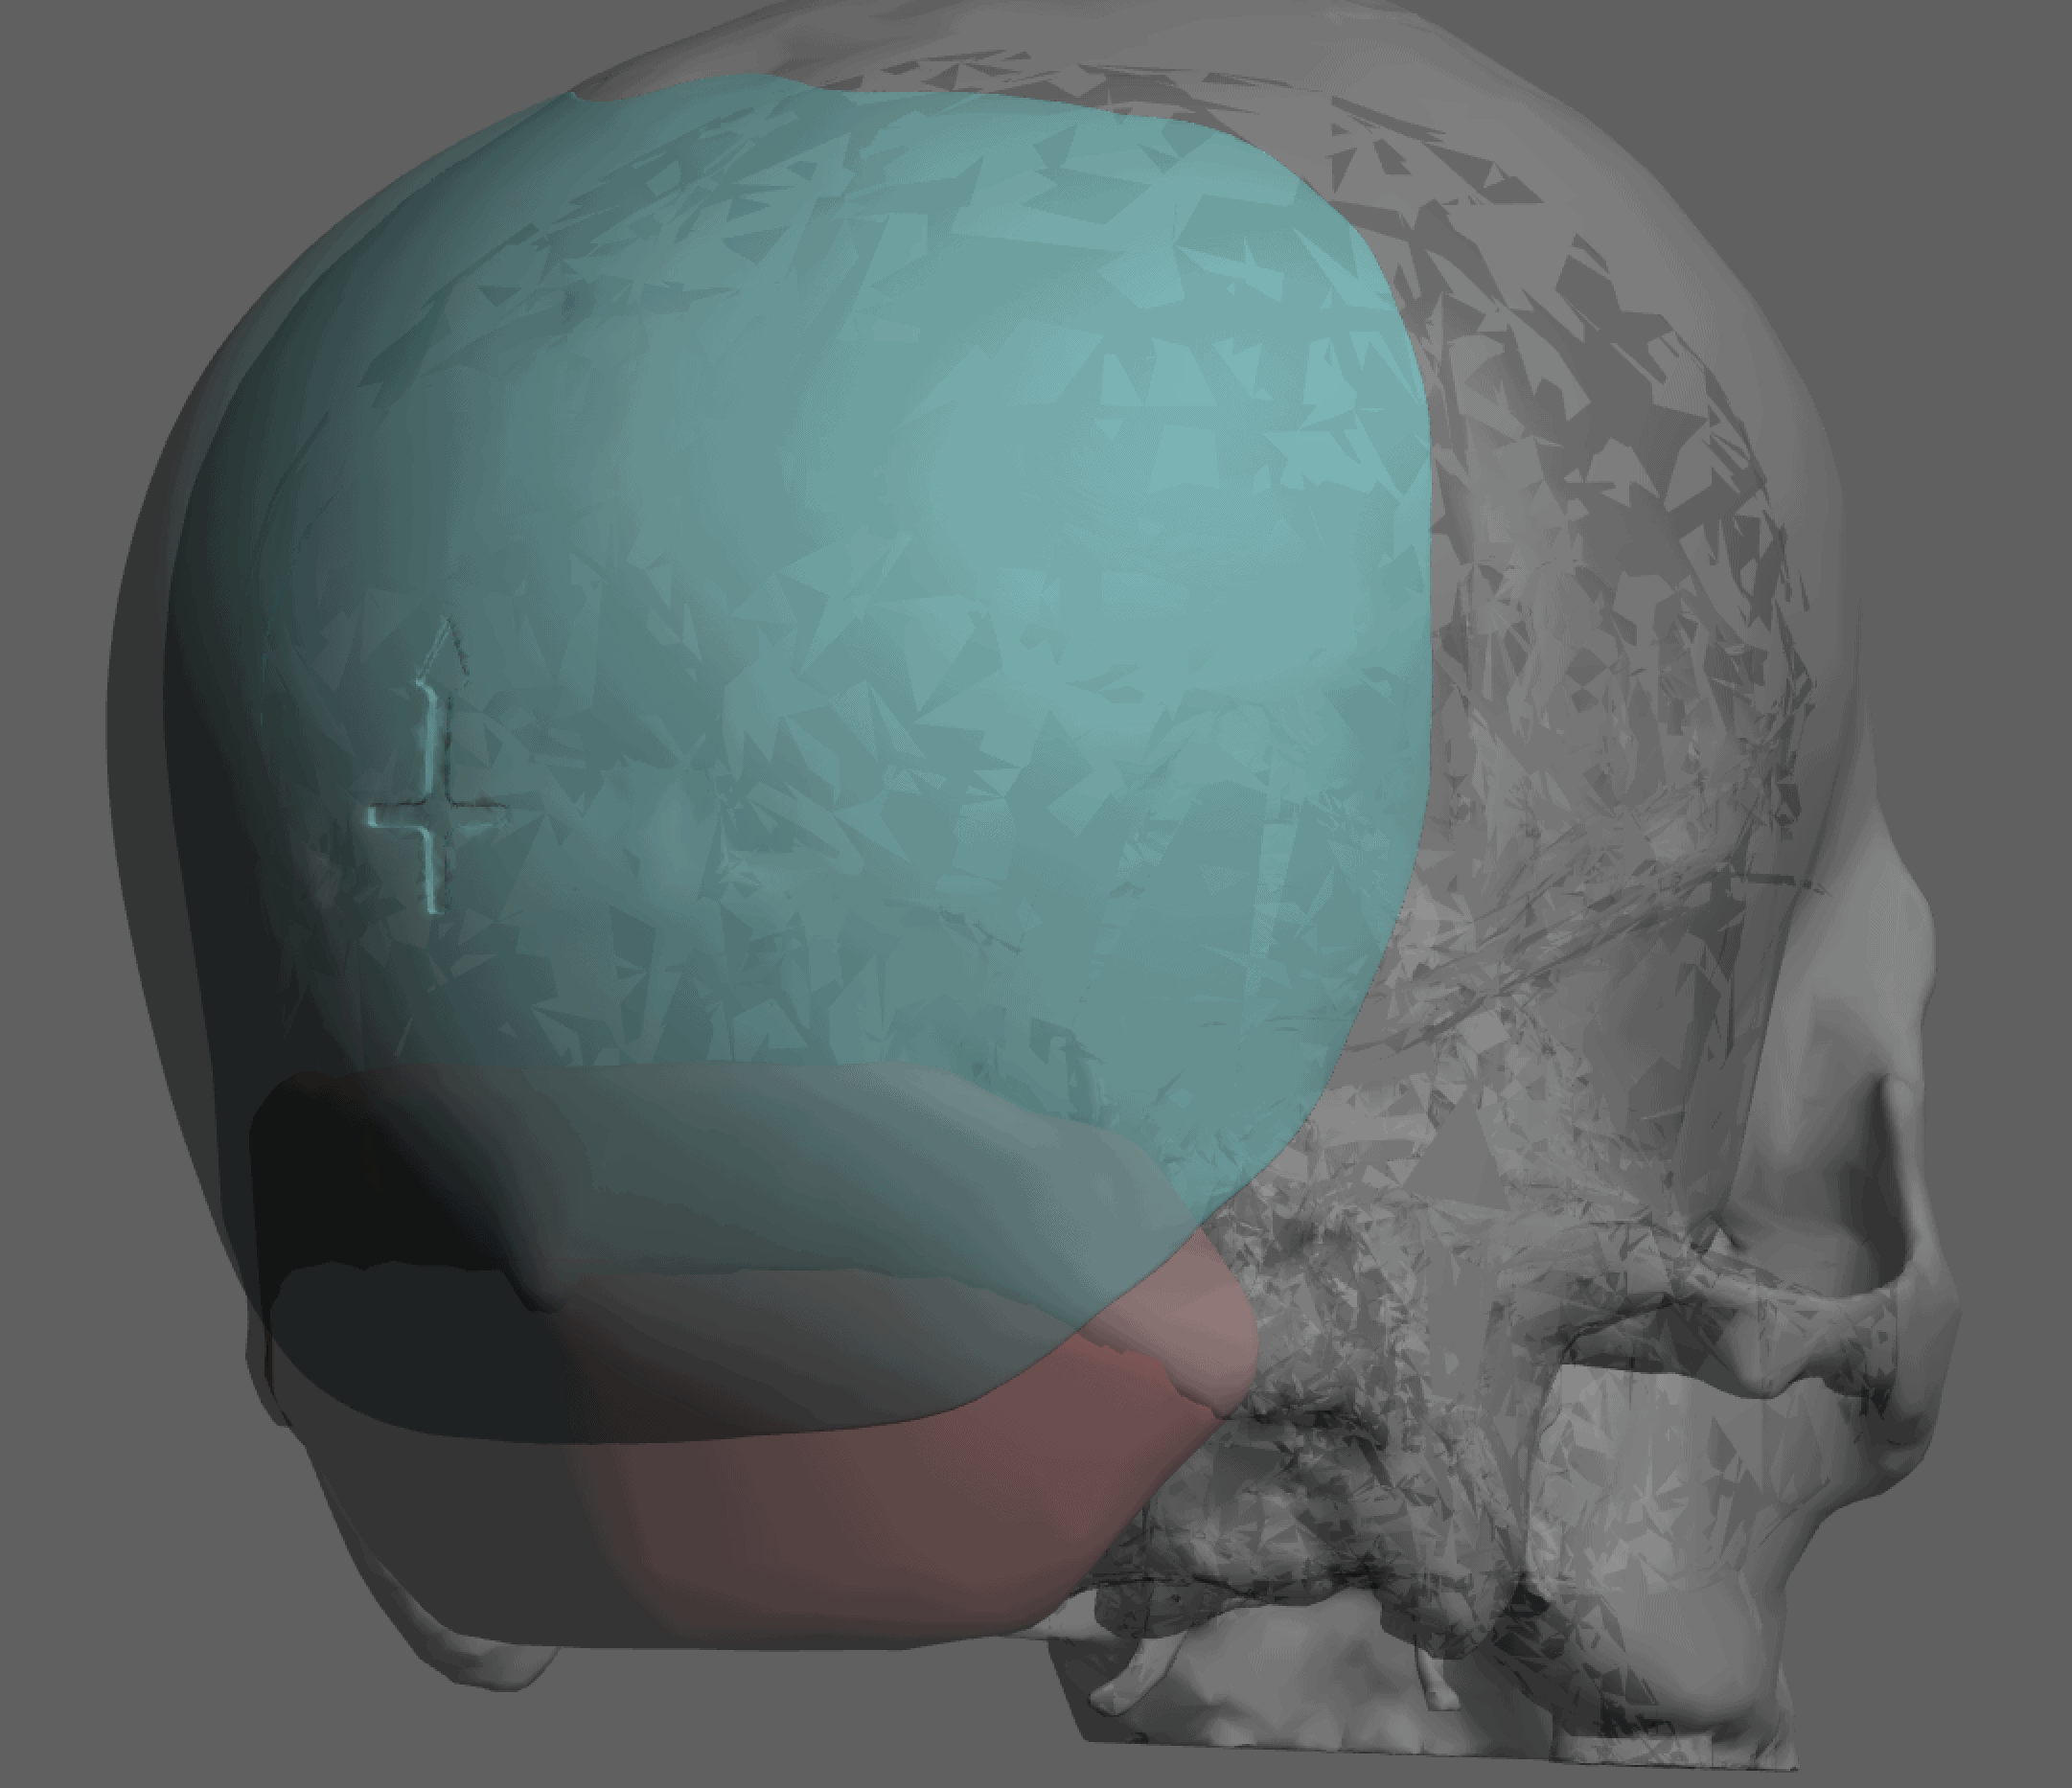

Patient 84

Desire for change of head shape from front view form an inverted V shape to a rounder and wider head shape.

Placement of custom extended forehead-temporal implants through incisions in the crease behind the ear. (he had a prior back of head skull implant which is green in the implant designs and which the head widening implants partially covered it)

Desire for change of head shape from front view form an inverted V shape to a rounder and wider head shape.

Placement of custom extended forehead-temporal implants through incisions in the crease behind the ear. (he had a prior back of head skull implant which is green in the implant designs and which the head widening implants partially covered it)